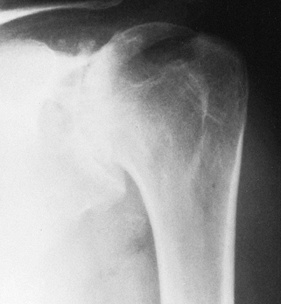

Rheumatoid arthritis, which usually affects the glenoid and humeral head (Fig. 101.10)

Figure 101.10. Rheumatoid arthritis of the glenohumeral joint. -